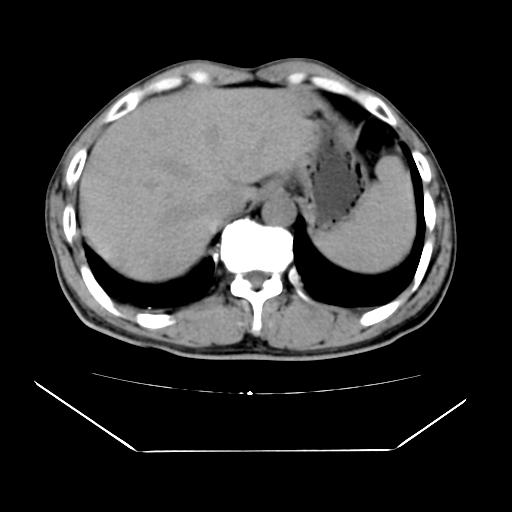

男性,55岁,外院体检afp明显升高,但b超未发现异常,否认乙肝病史。来我院ct增强。有延时扫描。

延时扫描完全充填,血管瘤

肝脏右叶动脉期可见低密度影,至延迟期被充填,考虑血管瘤可能性大。

肝右叶病灶

不排除肝右叶肝癌可能。

如果这个是癌灶的话则下腔静脉有瘤栓可能

肝6段血管瘤

血管瘤可能性大。

考虑肝右静脉影。